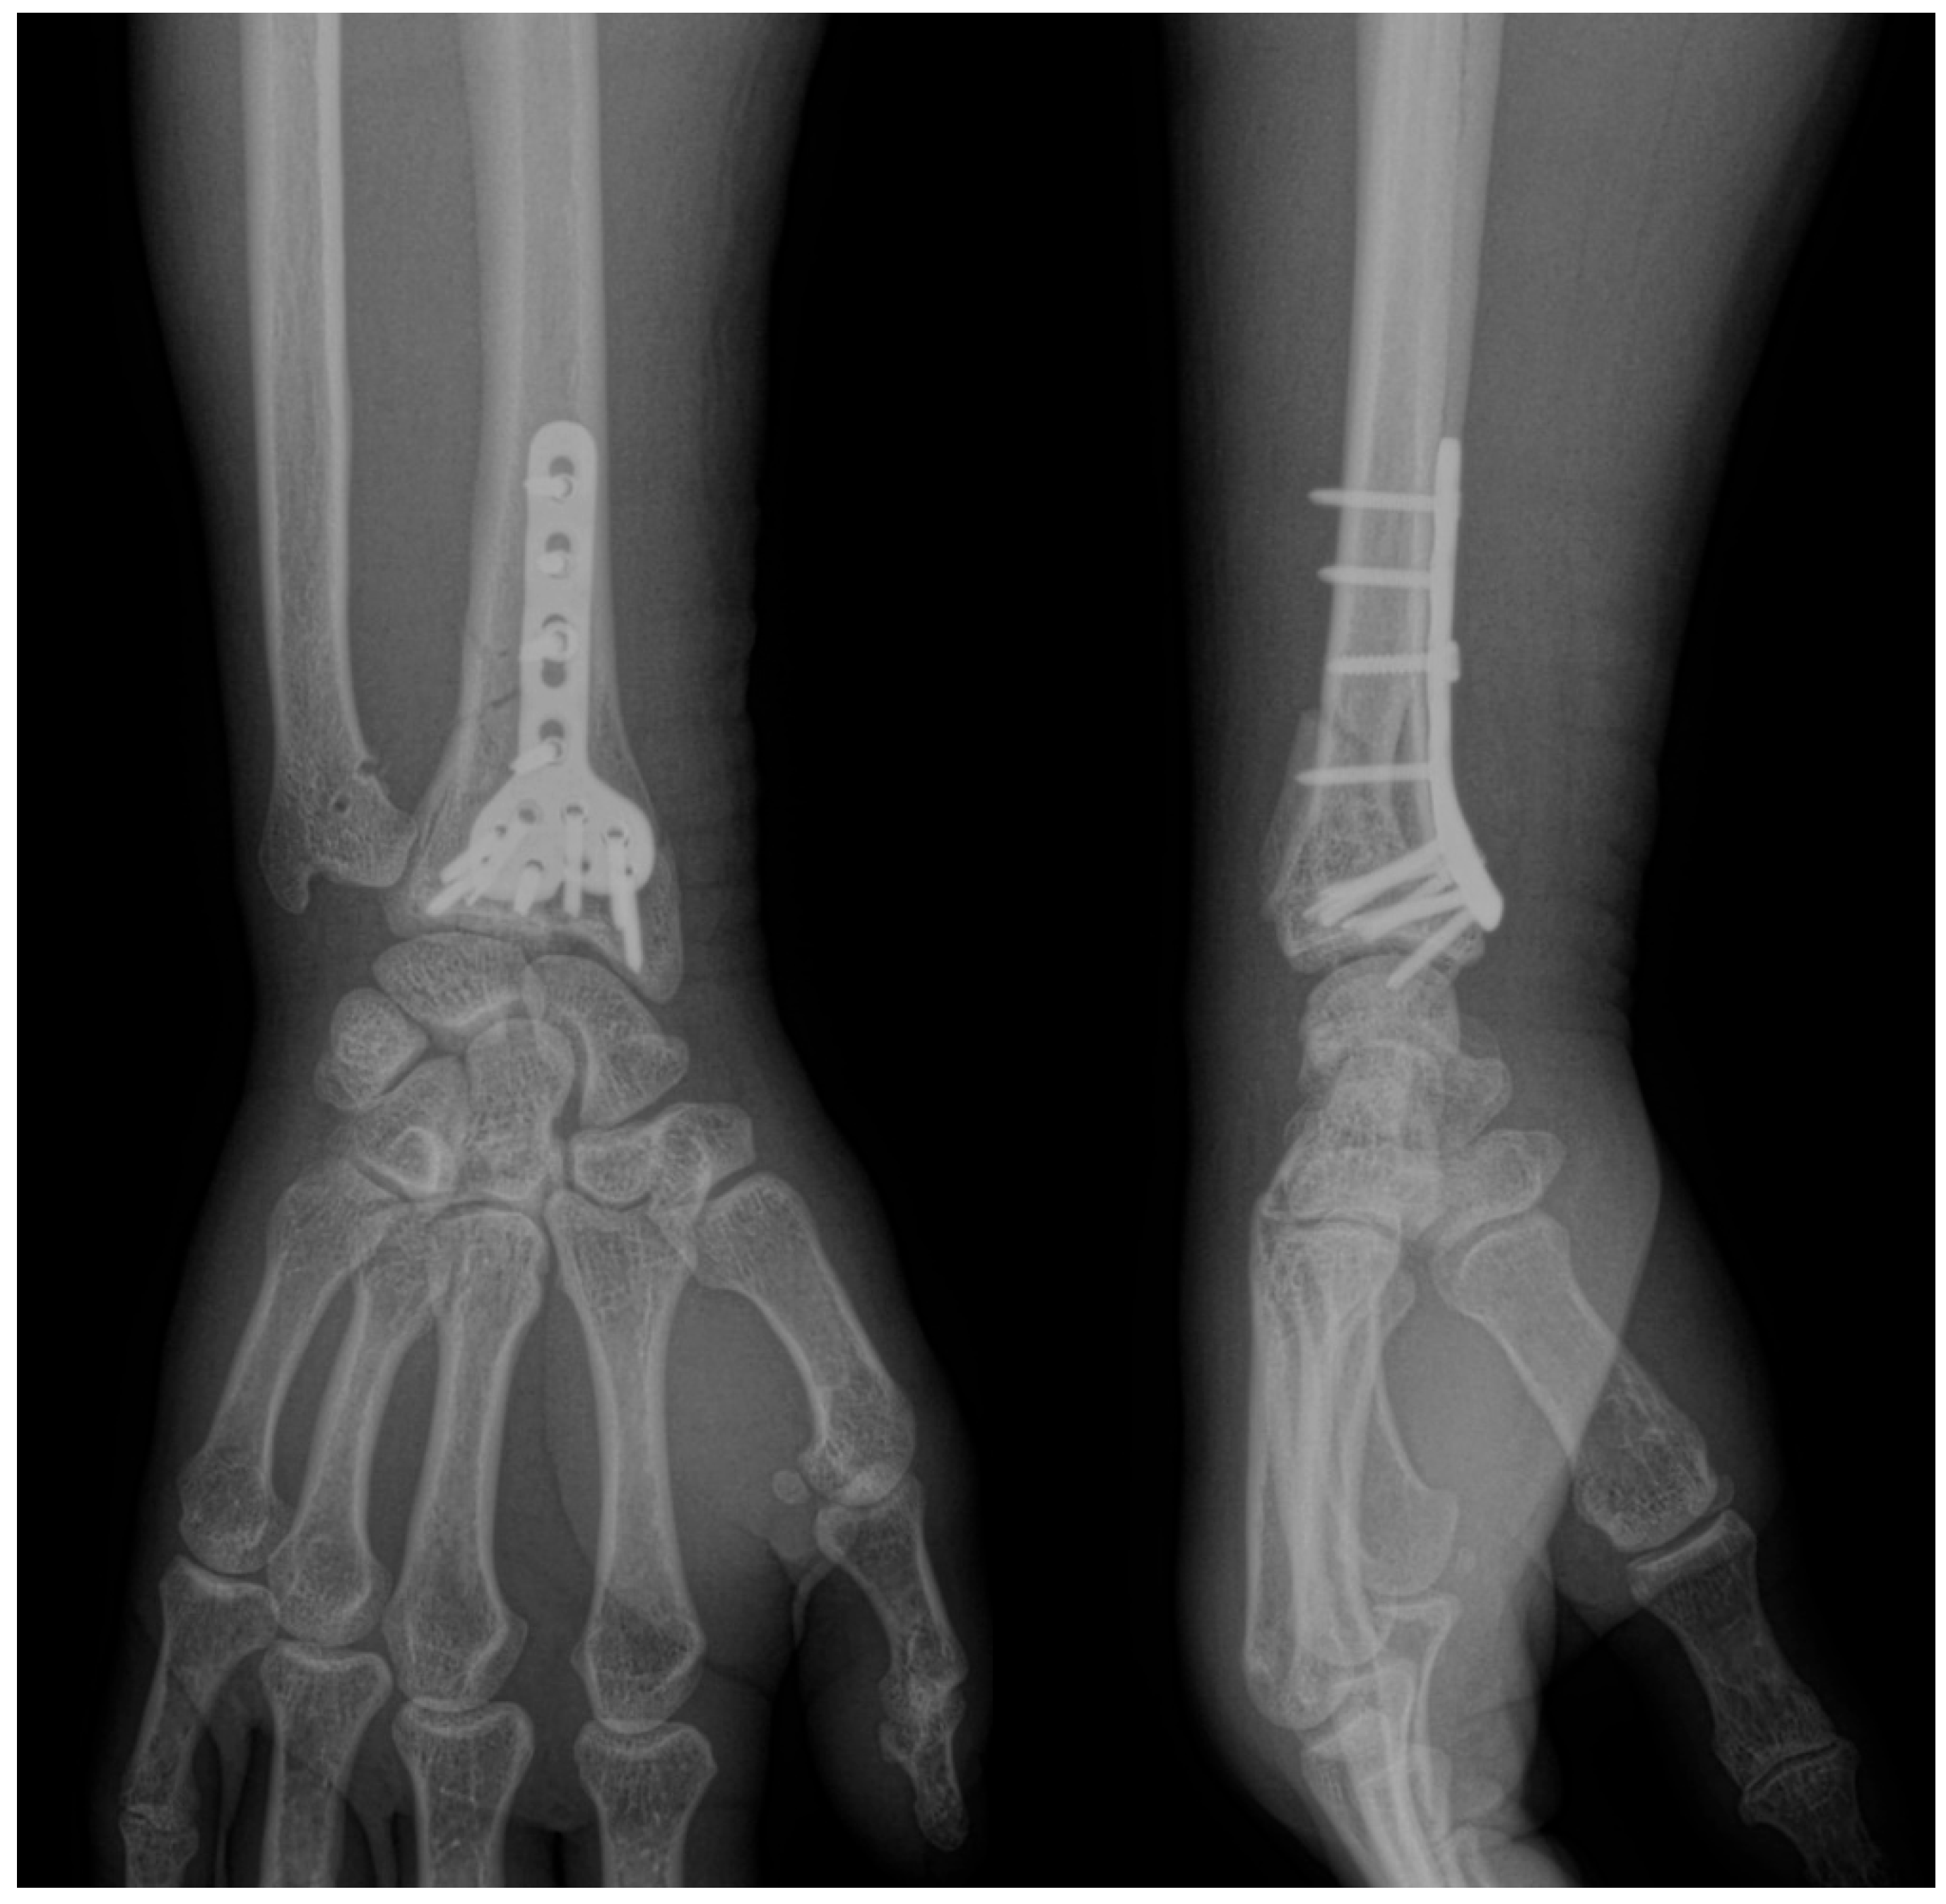

Two primary surgical techniques are commonly used to manage distal radius fractures (DRFs): open reduction with volar plates (Figure 1) and percutaneous fixation using Kirschner wires (K-wires) (Figure 2) [5]. While volar plates are frequently adopted for their advantages [6], K-wire fixation remains a viable alternative due to its reduced procedure duration and lower associated costs. However, there is ongoing debate regarding the optimal number, size, and configuration of K-wires necessary for effective fracture stabilization, with the biomechanical properties of various arrangements largely underexplored [5,7].

Figure 1. Anteroposterior and lateral views of distal radius fractures fixed with a volar locking plate.